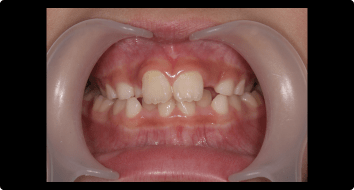

症例1:受け口の矯正治療

BEFORE

AFTER

症例概要

年代・性別

10歳代 女性

主訴

上下反対の噛み合わせが気になる

治療内容

ムーシールドを用いた矯正治療

治療期間

4ヶ月

治療のリスク

装置の装着時間を守らないと、治療結果が伴わない場合があります

治療費用

440,000円(税込)